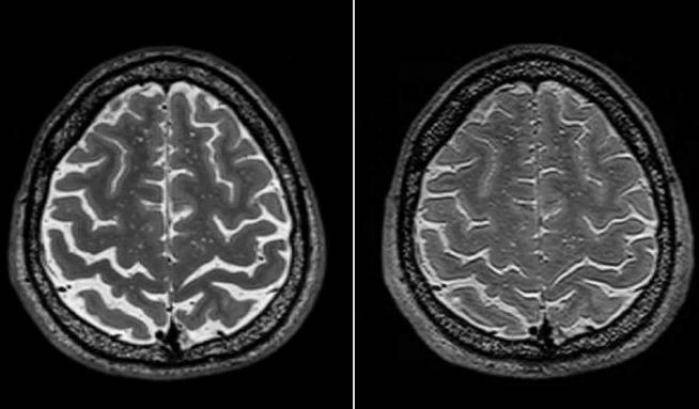

Cosa accade al cervello degli astronauti nello spazio? Questa domanda è oggetto di continue ricerche da parte degli scienziati. Un nuovo studio, condotto da un team di ricercatori guidato da Donna Roberts, neuro-radiologa alla Medical University of South Carolina, ha indagato ulteriormente sui cambiamenti che potrebbe subire la struttura cerebrale degli astronauti durante la permanenza nello spazio – ne abbiamo parlato qui per la prima volta. Come sappiamo, l’esposizione prolungata ad un ambiente di microgravità ha effetti permanenti sugli esseri umani, che ancora non riusciamo ancora a comprendere a pieno. Il team ha esaminato i dati delle risonanze magnetiche di 19 astronauti Nasa, osservando cambiamenti strutturali diffusi nel cervello, specialmente dopo missioni di lunga durata. Questi cambiamenti sembrano essere correlati alle variazioni nelle capacità motorie degli astronauti e nelle loro prestazioni cognitive durante i test post-volo.

I risultati mostrano che gli effetti a lungo termine di questi cambiamenti cerebrali sono ancora sconosciuti, a causa di mancanza di immagini più dettagliate. Ad oggi gli scienziati possono solo affermare quali sono le conseguenze nel breve periodo. Gli studi sul tema continueranno a ritmo serrato, per aiutare a identificare i problemi chiave nella pianificazione dell’esplorazione spaziale di più lunga durata, incluse le missioni su Marte.